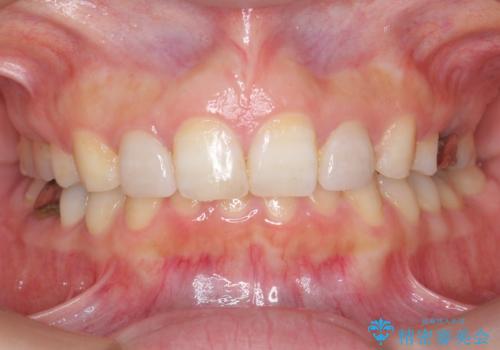

出っ歯を治したい 過蓋咬合

上顎2番は矮小歯だったのをセラミックで被せています。

- 矯正治療85万円 補綴治療16万円(emaxクラウン、仮歯)費用は治療当時の料金となります

口唇の突出感がなくなり、理想的な横顔になりました。

虫歯治療は、他院で保険治療で行なって頂いています。